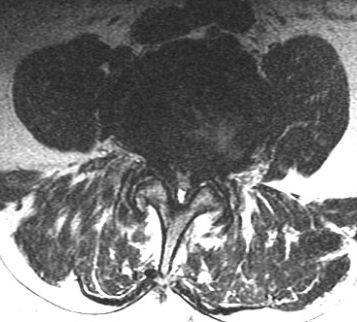

Lendenwirbelsäule

Auch hier reicht zumeist Röntgenaufnahme in Funktion sowie eine Kernspintomographie oder eine Computertomographie aus. Bei einem Wirbelgleiten oder einer Verengung auf mehreren Höhen ist eine Myelographie nach wie vor die Untersuchung, die die wertvollsten Ergebnisse im Hinblick auf eine genaue Operationsplanung liefert.